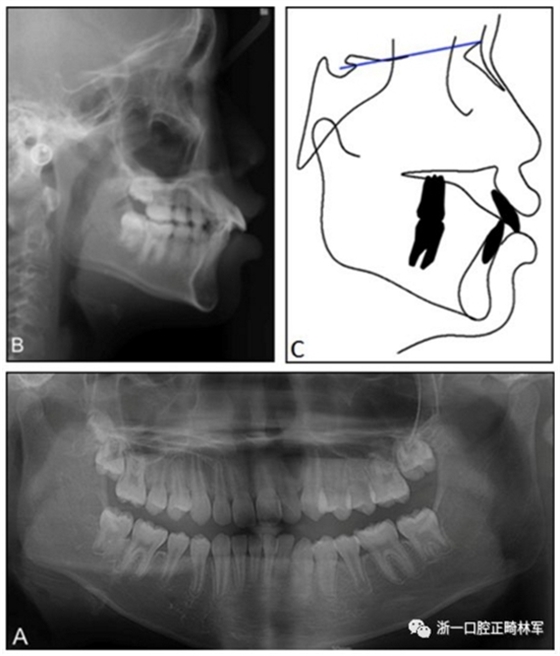

患者男,10歲11個月,主訴嘴突。側(cè)貌突面型,上下嘴唇凸起。開唇露齒,上唇短??趦?nèi)示,中線齊,覆蓋7mm,II度深覆合,雙側(cè)磨牙關(guān)系I類,尖牙關(guān)系II類。上頜牙弓輕度擁擠,下頜牙弓中度擁擠,spee曲線深,上頜第二磨牙未萌。

X線頭影測量分析示安氏I類(ANB,3.5°;Wits,–1.5mm),低角型(FMA,23),上下頜切牙前傾(U1-FH,121°,IMPA,96°)。